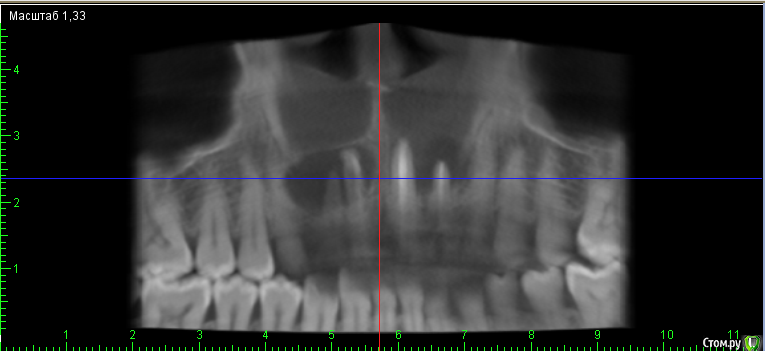

___49___ Опубликовано 5 декабря, 2016 Поделиться Опубликовано 5 декабря, 2016 Что скажите коллеги - интересно ваше мнение , советы. 11 зуб - канал разбит - пока не решил, что с ним делать. Остальные зубы однозначно хочу оставить + эндо 12 му. А после резекция..... Ссылка на комментарий

___49___ Опубликовано 7 декабря, 2016 Автор Поделиться Опубликовано 7 декабря, 2016 Да, интересный случай. А прицельные снимки есть?Да прицельные есть, но по моему они не более информативны чем представленное ОПГ . Если нужно - выложу прицельные.? Ссылка на комментарий

DmitrySH Опубликовано 7 декабря, 2016 Поделиться Опубликовано 7 декабря, 2016 Да прицельные есть, но по моему они не более информативны чем представленное ОПГ . Если нужно - выложу прицельные.? всегда смотрю и то и другое. Сказали же, канал у 11 разбит. Так хороший прицельный снимок тут может быть более информативен чем КТ. Ссылка на комментарий